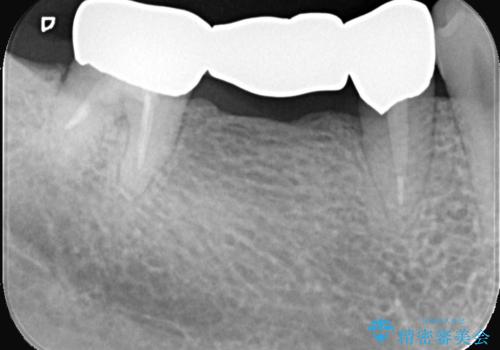

- 主訴:つい先日入れたセラミック(ジルコニア)ブリッジが奥歯部分で割れた。いつも同じ場所で壊れる。これで3度目。

セラミックに比べ、割れづらい金属(ゴールドでのブリッジのやり替えとなりました。

セラミックに比べ、破折リスクの少ない金属を使用したブリッジでのやり替えとなりました。

両支台歯が失活歯のため、どちらかもしくは両方の歯が破折した際、再度ブリッジを除去した治療が必要になるリスクとインプラント治療のご提案もさせていただきましたが、ブリッジでの治療を希望されました。

右下5番は支台歯CR築造を行っています。